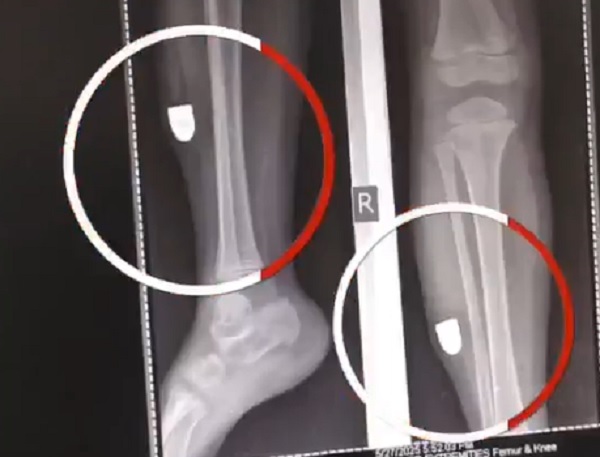

ਇਸ ਸਬੰਧੀ ਮੀਡੀਆ ਨੂੰ ਜਾਣਕਾਰੀ ਦਿੰਦਿਆਂ ਜ਼ਖਮੀ ਬੱਚੀ ਦੇ ਪਿਤਾ ਨੇ ਦੱਸਿਆ ਕਿ ਉਹ ਆਪਣੀ ਬੇਟੀ ਵਿਰਧੀ ਨੂੰ ਲੈ ਕੇ ਟਿਊਸ਼ਨ 'ਤੇ ਜਾ ਰਹੇ ਸਨ ਤਾਂ ਇਸ ਦੌਰਾਨ ਪਟਾਕੇ ਦੀ ਆਵਾਜ਼ ਆਈ ਅਤੇ ਉਸਦੀ ਬੱਚੀ ਦੇ ਲੱਤ 'ਚੋਂ ਖੂਨ ਨਿਕਲਣਾ ਸ਼ੁਰੂ ਹੋ ਗਿਆ ਜਿਸ ਤੋਂ ਬਾਅਦ ਉਹ ਉਸਨੂੰ ਇਲਾਜ ਲਈ ਕਲੀਨਿਕ ਲੈਕੇ ਗਏ ਤੇ ਬਾਅਦ ਵਿੱਚ ਹਸਪਤਾਲ਼ ਖੜਿਆ ਤੇ ਉੱਥੇ ਜਾ ਕੇ ਐਕਸਰਾ ਕਰਵਾਉਣ ਤੇ ਪਤਾ ਚੱਲਿਆ ਕਿ ਉਸ ਦੀ ਬੱਚੀ ਦੀ ਲੱਤ ਵਿੱਚ ਗੋਲੀ ਵੱਜੀ ਹੈ। ਜਿਸ ਤੋਂ ਬਾਅਦ ਉਨ੍ਹਾਂ ਵੱਲੋਂ ਪੁਲਸ ਨੂੰ ਦਰਖਾਸਤ ਦਿੱਤੀ ਗਈ ਅਤੇ ਹੁਣ ਮੰਗ ਕੀਤੀ ਗਈ ਕਿ ਜਿਨ੍ਹਾਂ ਵੱਲੋਂ ਅਜਿਹੀ ਹਰਕਤ ਕੀਤੀ ਗਈ ਹੈ ਉਨ੍ਹਾਂ ਖਿਲਾਫ ਸਖਤ ਕਾਰਵਾਈ ਕੀਤੀ ਜਾਵੇ।

ਦੂਜੇ ਪਾਸੇ ਇਸ ਸਬੰਧੀ ਥਾਣਾ ਗੇਟ ਹਕੀਮਾਂ ਦੇ ਪੁਲਸ ਅਧਿਕਾਰੀ ਨੇ ਮੀਡੀਆ ਨੂੰ ਜਾਣਕਾਰੀ ਦਿੰਦੇ ਹੋਏ ਦੱਸਿਆ ਕਿ ਸਾਡੇ ਤਿੰਨ ਸਾਲ ਦੀ ਬੱਚੀ ਦੀ ਲੱਤ 'ਤੇ ਗੋਲੀ ਵੱਜਣ ਦਾ ਮਾਮਲਾ ਸਾਹਮਣੇ ਆਇਆ ਹੈ ਅਤੇ ਜਦੋਂ ਇਹ ਘਟਨਾ ਵਾਪਰੀ ਅਤੇ ਪਰਿਵਾਰ ਨੂੰ ਵੀ ਨਹੀਂ ਪਤਾ ਚੱਲਿਆ ਕਿ ਬੱਚੀ ਦੀ ਲੱਤ 'ਤੇ ਗੋਲੀ ਵੱਜੀ ਹੈ। ਜਦੋਂ ਹਸਪਤਾਲ 'ਚ ਆਉਣ 'ਤੇ ਐਕਸਰਾ ਕਰਵਾਇਆ ਗਿਆ ਤੇ ਫਿਰ ਪਤਾ ਚੱਲਿਆ ਕਿ ਲੱਤ ਵਿੱਚ ਗੋਲੀ ਵੱਜੀ ਹੈ। ਫਿਲਹਾਲ ਪਰਿਵਾਰ ਨੂੰ ਨਾਲ ਲੈ ਕੇ ਮੌਕੇ 'ਤੇ ਜਾ ਰਹੇ ਹਾਂ ਅਤੇ ਇਸ ਮਾਮਲੇ ਦੀ ਜਾਂਚ ਕੀਤੀ ਜਾ ਰਹੀ ਹੈ ਤੇ ਮੁਲਜ਼ਮਾਂ ਖਿਲਾਫ ਕਾਨੂੰਨ ਮੁਤਾਬਿਕ ਕਾਰਵਾਈ ਕੀਤੀ ਜਾਵੇਗੀ।